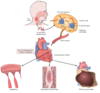

Dilated Cardiomyopathy

Globoid shape because all chambers are dilated. Feels flabby & myocardium is poorly contractile.

Cardiomyopathy = poorly functioning myocardium and heart is large and dilated, but no specific histologic findings

Dilated cardiomyopathy

Large, dilated LV

Dilated Cardiomyopathy

Dilated Cardiomyopathy

Cardiomyopathy

Microscopically, heart demonstrates hypertrophy of myocardial fibers (prominent dark nuclei) + interstitial fibrosis